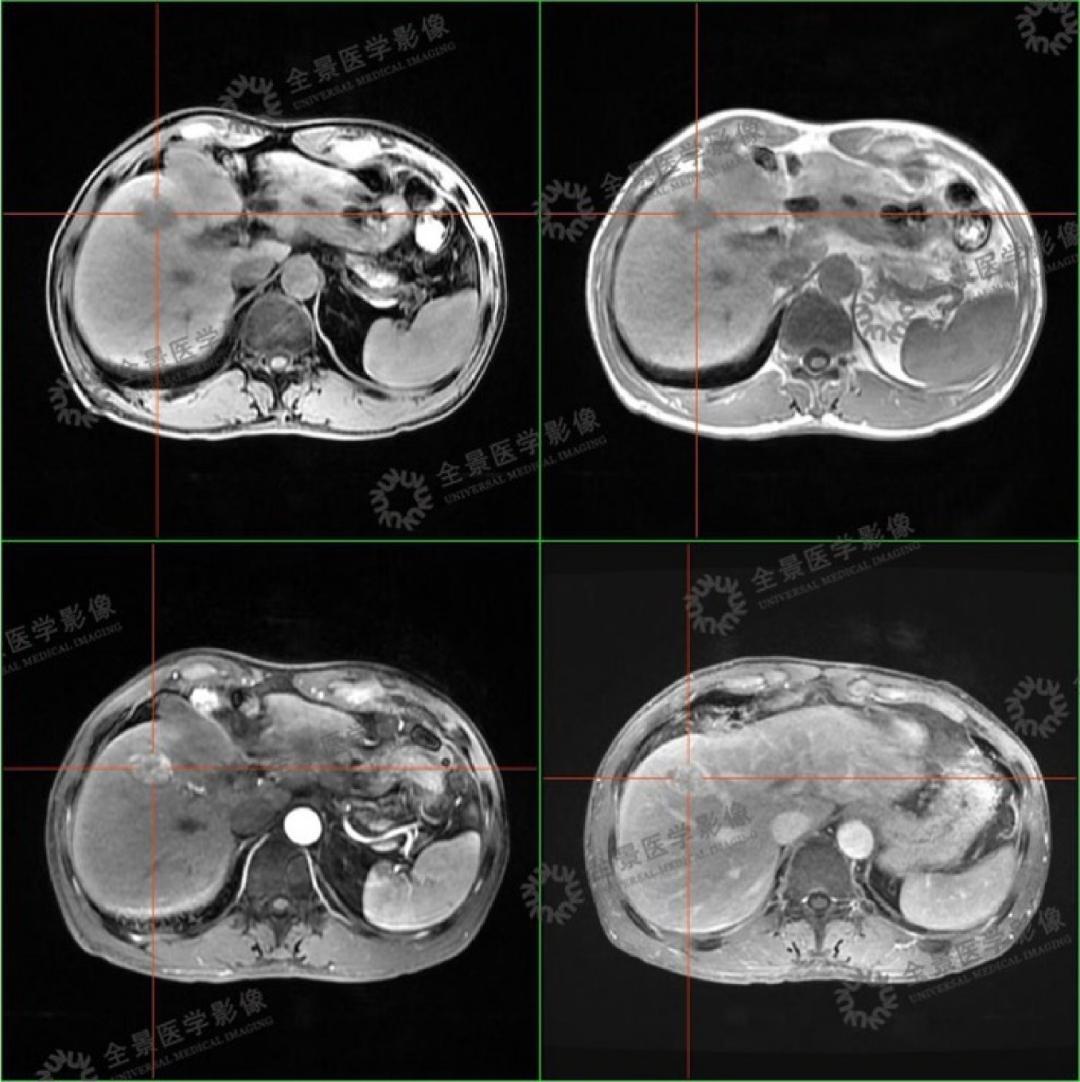

不出意外的,磁共振再次确认了我的肝部有团块状的阴影,增强扫描持续强化。

PET/CT结果出来后,全景又与我的磁共振检查图像进行融合,最后诊断为肝癌。